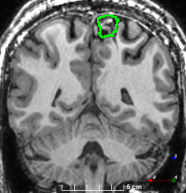

Refer to caption

(a)

(b)

(c)

(d)

(e)

(f)

Figure 3: Manual labels from Rater A (green) and Rater D, the model trained with PubFull + EpiPre + Pseudo (magenta). Errors caused by a (a) small resection, (b) blood clot in cavity and (c) brain shift; segmentations corresponding to the (d) 50th, (e) 75th and (f) 100th percentiles giving a DSC of 81.7, 86.5 and 93.8, respectively.

We trained a model using PubFull, EpiPre and Pseudo (2371 images), obtaining a DSC of 81.7 (14.2). Adding the pseudo-labels to PubFull and EpiPre did not significantly improve performance (p=0.176𝑝0.176p=0.176), indicating our semi-supervised learning approach provided no advantage. Predictions from this model are shown in Fig. 3.